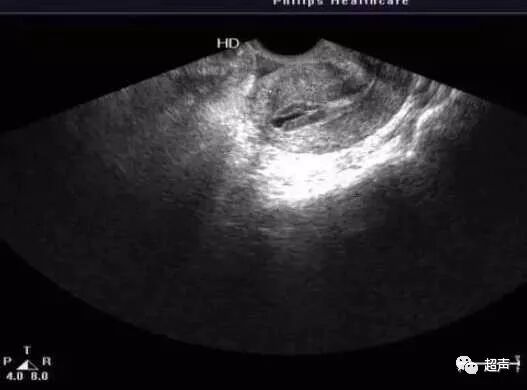

B型内膜常见于内膜增生晚期(排卵前后),排卵时内膜厚度约为9-12mm,为均一的中等强回声,宫腔强回声中线断续不清。

B型内膜